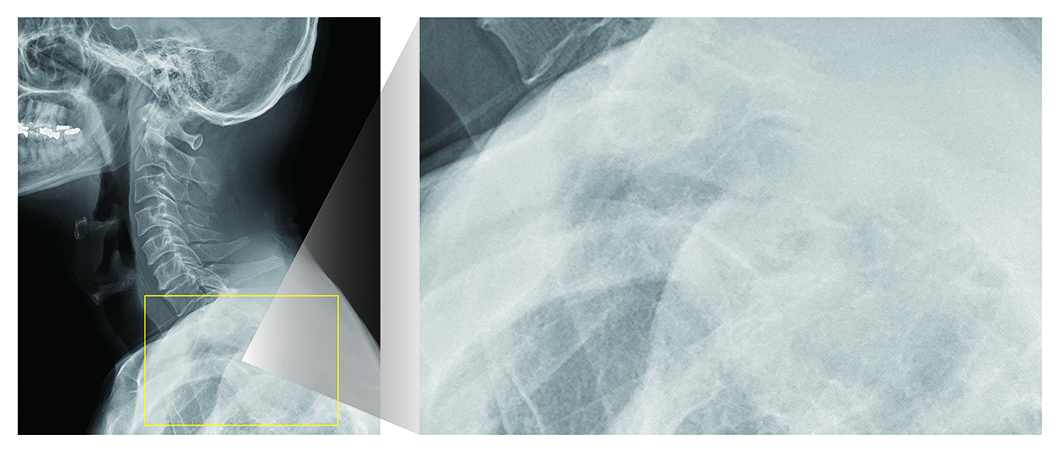

カテ先・ガーゼ強調処理

ポータブル撮影における残存物確認や、カテーテルの先端位置、ルート確認をしやすくするための 専用画像処理を搭載しています。 適用対象部位を拡大したことにより、ガラス片の確認や、胆道造影、 椎体の穿刺画像など多様なシーンでその効果が期待できます。

<対象部位>

頭部(正面・側面・タウン)/聴器/頸部(正面・側面・斜位)/頸椎(正面・側面・斜位)/胸部(正面・側面)/胸椎(正面・側面)・腰椎(正面・側面・斜位)・腹部(正面/側面)/膀胱造影/手指骨/足根骨/足趾/足指骨/小児胸部(正面・側面)/乳幼児(胸腹部)/新生児(胸腹部)